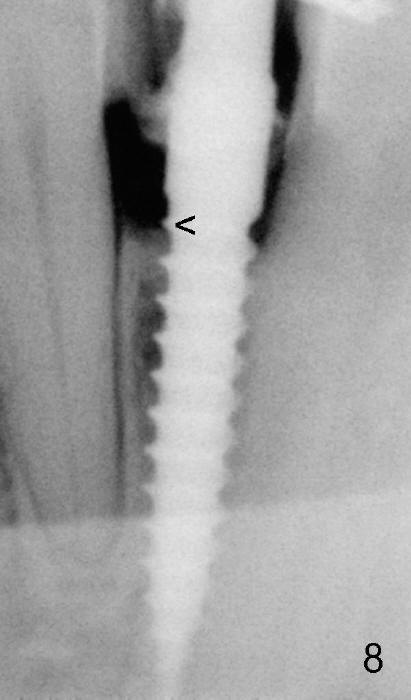

Fig.8: 2 years 2 months postop, still not permanently restored. The 1st thread is now supracrestal. The implant crown remains normal 1 year 10 months post 2nd cementation (4 years 10 months postop, Fig.13).